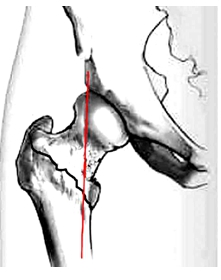

传统的髋关节前侧入路(Smith-Peterson入路)起自髂嵴中部,沿髂嵴外侧向前至髂前上棘,然后向远端延伸,深层沿阔筋膜张肌和缝匠肌间隙分离,自髋臼上方切断股直肌指头并翻转,显露髋关节囊(图1A,B)。

这种切口创面大,手术剥离广泛,不利于患者的术后恢复。因此,我们SP切口的特点设计一直切口,即仅使用传统切口的远侧部分,自髂前上棘内侧及下方各1.5cm处向远端做一10cm纵切口(图2),浅层沿阔筋膜张肌和缝匠肌之间钝性分离,深层间隙位于臀中肌和股直肌之间(图3A)。治疗股骨粗隆间骨折时仅需将股直肌牵向内侧而无需切断,股骨颈骨折可根据术野显露情况决定是否切断股直肌(图3B,C)。随后在股骨颈上、下缘及股骨大粗隆外侧各放置一把Hoffman拉钩,显露股骨近端的前方(图4)。该入路既保留了髋关节前侧入路显露充分的优点,同时又减少了对髋部肌肉组织的破坏,有利于患者的术后康复。同时,稍偏内的切口也有助于降低股前外侧皮神经损伤的机率。